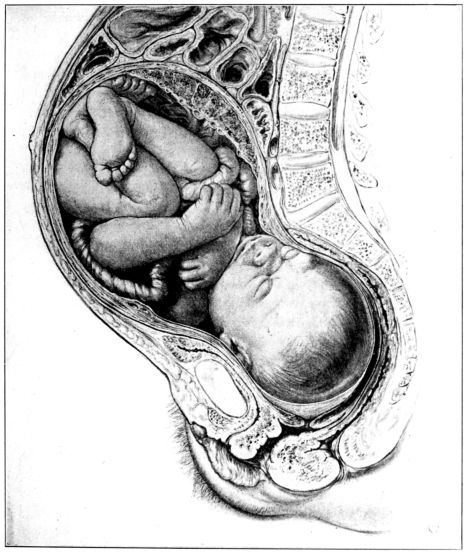

| 27. | Full term fetus in utero | 81 |

| xx28. | Diagram of fetal circulation | 85 |